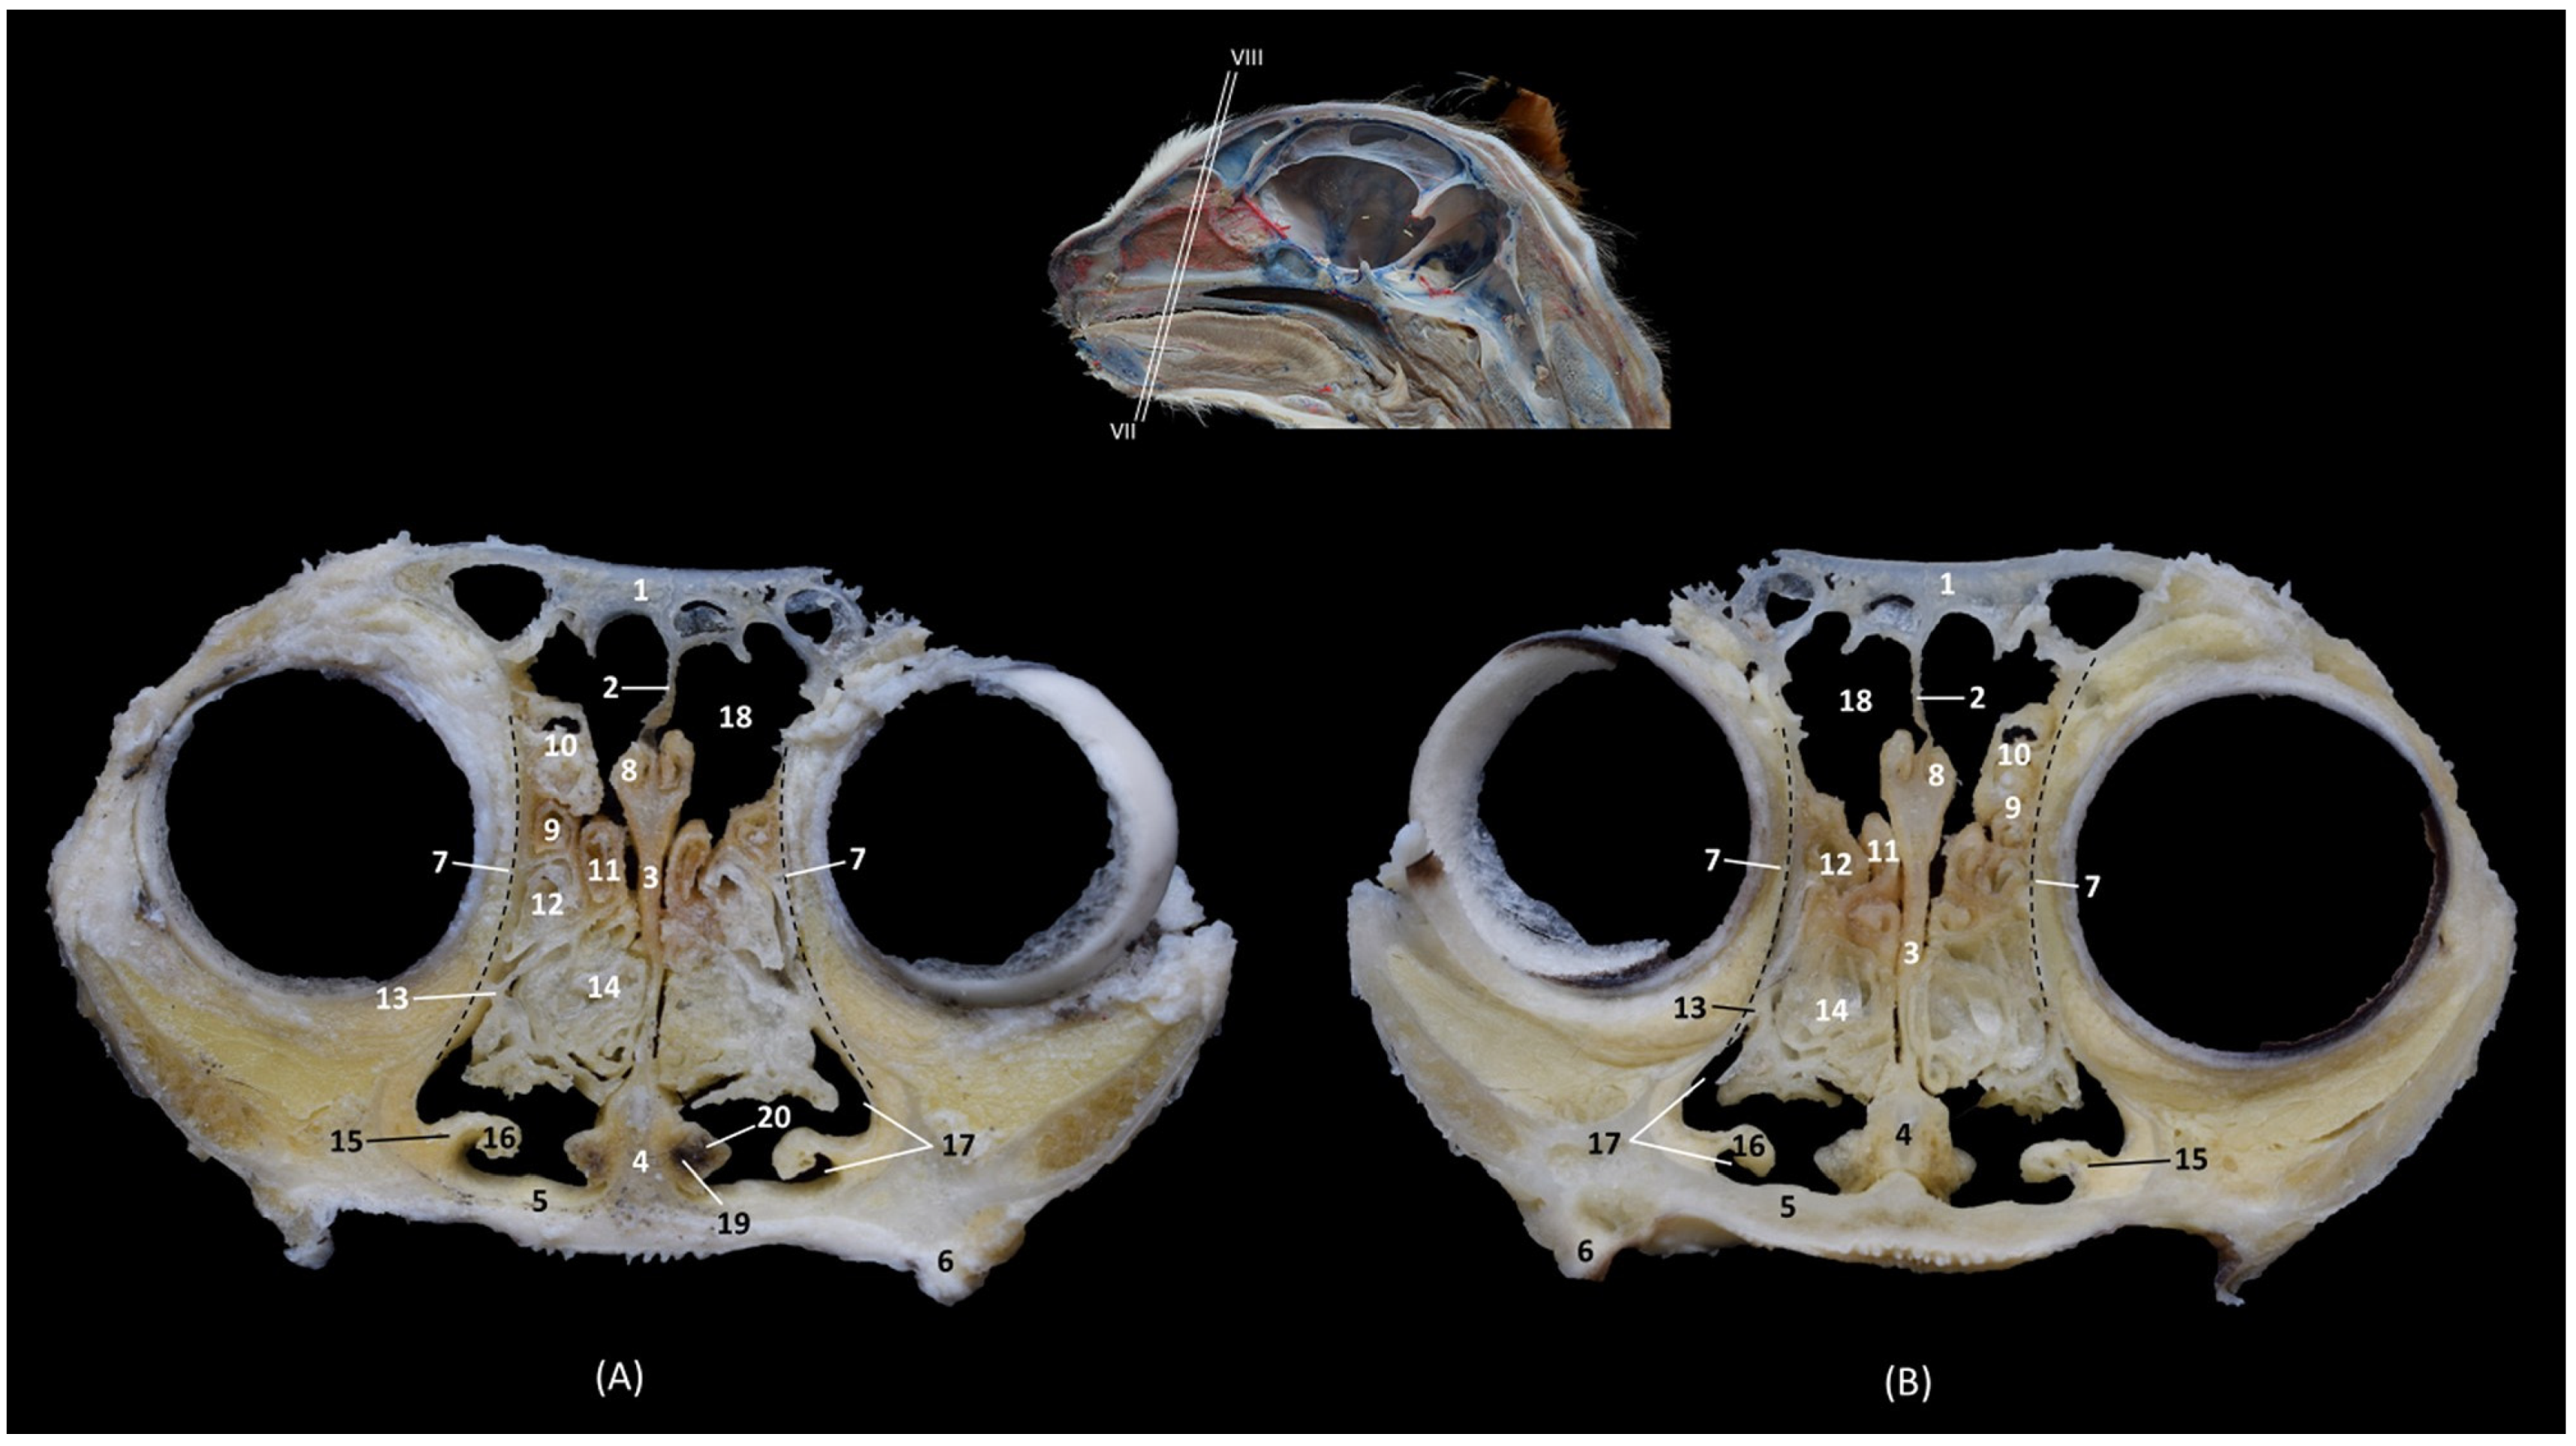

In Figure 2, the maxilla was dissected to observe that the ventral nasal concha, which is feather-shaped, is short and is only attached to the maxilla. After resecting the maxilla, it can be observed how the dorsal and middle conchae and the third and fourth endoturbinates are connected to the ethmoid bone and are independent of the maxilla.

3.2. Trepanations

The two domestic cat skulls with trepanations presented in this study allowed us to identify the entire origin and route of the ethmoturbinates, as well as the bones that support the bony nasal cavity. After cutting part of the orbital surface of the frontal bone, and the wings of the basisphenoid and presphenoid bones, the origin of the three ectoturbinates can be visualized from the tectorial plate of the ethmoid bone. The first and the second ectoturbinates reach great development on their medial side, while the third is sometimes camouflaged between the other two, since it develops more laterally. The three ectoturbinates were delimited dorsally and ventrally by the tectorial plate of the ethmoid bone (Figure 3B). In this same image, below the dorsal and middle nasal conchae, the great development of the third endoturbinate and its trabeculated bone appearance can be seen. This endoturbinate covers the dorsal half of the medial face of the ventral nasal concha and its double origin in the ethmoid bone can be seen again on both its lateral (Figure 3C) and its medial faces (Figure 3B). The fourth endoturbinate, small in size, was located next to the sphenoid sinus. In the oblique views (Figure 3A,C,D), it was observed how these conchae reach the nasal vestibule, being very thin and fragile bony nasal conchae.